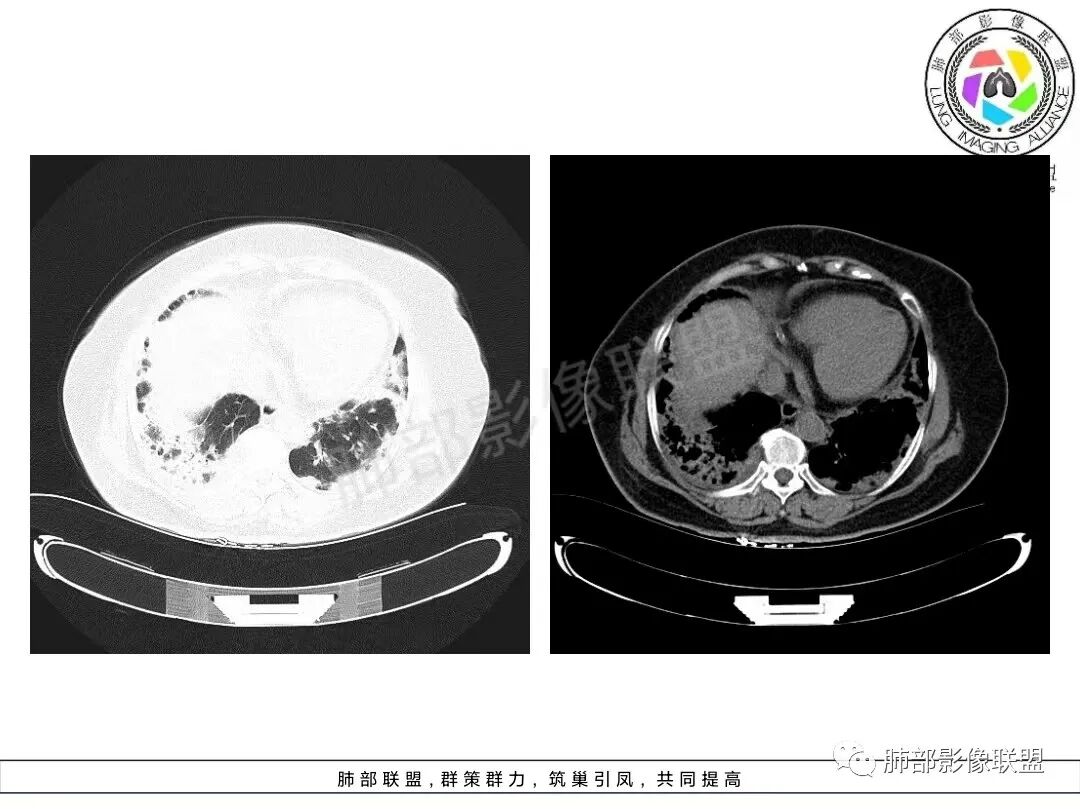

1、临床特点:70岁女性,务农。咳嗽咳痰伴气急20天。症状逐渐加重。有高血压病史。入院查体:体温37.5℃,急性面容。白细胞、CRP、红细胞沉降率升高。血糖高,CEA升高、余肿瘤标志物正常。ANCA检查阴性。血培养阴性,支气管灌洗液培养、真菌检测、抗酸杆菌均阴性。

2、影像特点:双肺胸膜下为主、多发斑片影、结节样实变影及磨玻璃样密度影,大部分病灶边缘平直、边界清,磨玻璃密度病灶内可见细网格影,部分病灶内可见支气管扩张表现,部分支气管直达远端,部分中断于病灶中部。部分病灶有侧向融合趋势。

3、病例小结:老年女性,咳嗽咳痰伴气急逐渐加重,入院后有低热。部分炎性指标升高,肺部片影,可以符合感染性病变,但是血培养、支气管灌洗液培养等检查无阳性表现。但仍影警惕隐球菌感染,患者临床表现相对轻微,胸膜下病灶,磨玻璃影等。

影像上双肺多发磨玻璃影及实行密度影,对称分布趋势,op样改变,结缔组织相关性疾病需要排除。临床上可进一步查皮肌炎相关指标、仔细进行体格检查看看患者皮肤等情况。